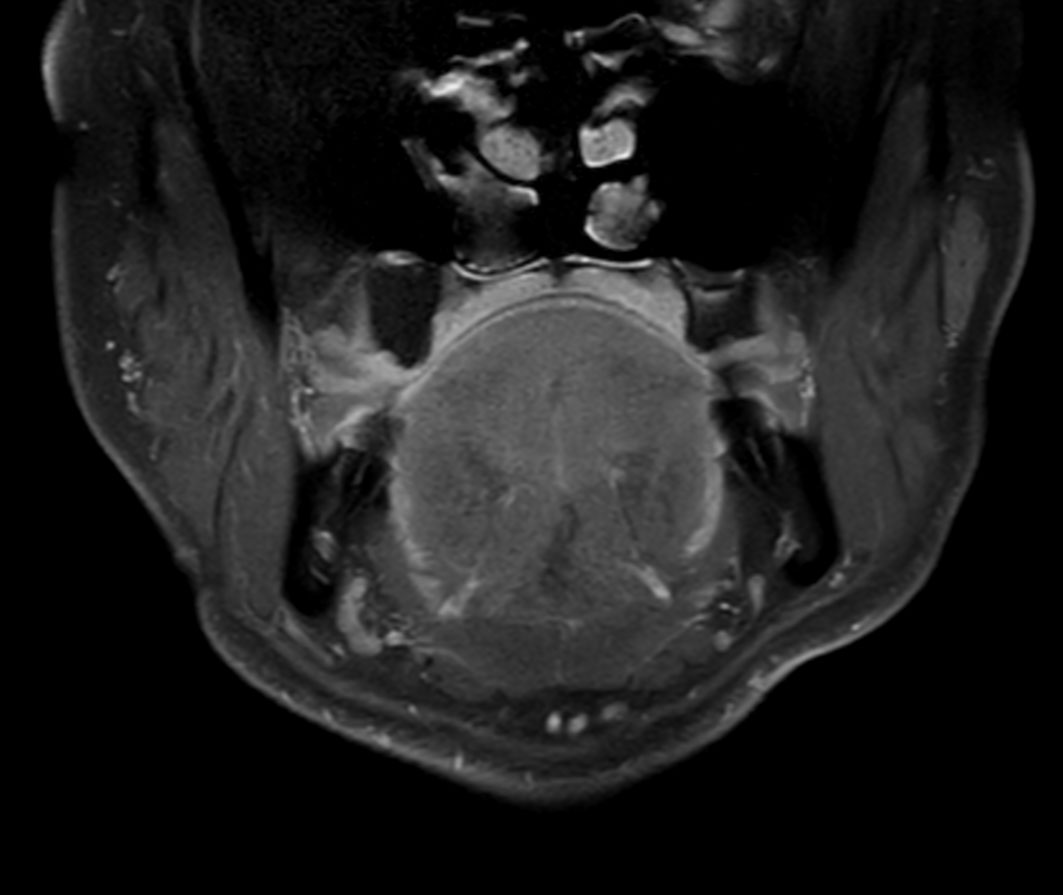

Axial STIR TSE